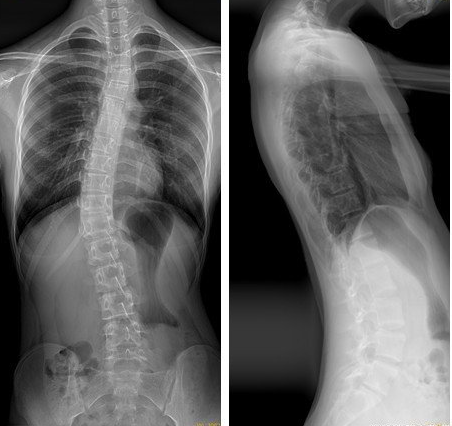

一镜到底看全身,全脊柱与双下肢DR拼接成像技术

试想,脊柱侧弯患者需要精准评估弯曲程度,膝关节疼痛的老人想要排查下肢整体力线,传统X光片需分段拍摄,受限于视野范围,可能需要多次调整体位;而现代DR拼接成像技术可实现连续拍摄,可有效解决这些难题,能为医生清晰呈现一幅完整的“全身骨骼地图”,为诊断提供更全面的影像支持,为骨骼系统整体评估提供了新的技术选择。

全脊柱拼接成像:挺直脊梁的全面评估

应用场景:

脊柱侧弯(评估Cobb角、旋转度)、脊柱后凸/前凸畸形、脊柱骨折脱位、脊柱术后力线评估、脊柱退行性疾病累及范围观察、生长发育评估。

独特价值:

一次成像即可清晰展现从颈椎到骶尾椎的整体生理曲度、力线排列和平衡状态,是有明确临床指征时,评估脊柱整体形态和制定矫形方案的重要参考依据。尤其对于脊柱侧弯患者,可精确测量角度,减少多次拍摄的辐射累积。